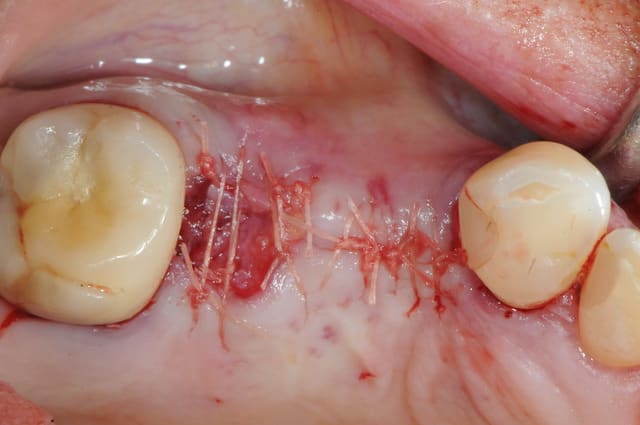

pour débuter ce post je propose un petit cas avec une ROG un comblement alvéolaire et un lambeau pédiculé pour fermer le site d'extraction.

> Quelles sont tes incisions pour le lambeau pédiculé palatin ?

au début incision supra crestal puis lambeau muco-périosté.

> Avec quels instruments réalises tu la dissection ?

avec une simple lame 11 qui tranche le long de gencive palatine. évidemment c'est le plus dure à faire pour éviter de transpercer ou d'avoir d'un coté ou de l'autre une épaisseur trop faible.